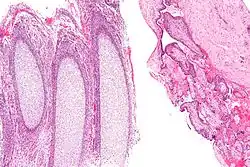

Products of conception, abbreviated POC, is a medical term used for the tissue derived from the union of an egg and a sperm. It encompasses anembryonic gestation (blighted ovum) which does not have a viable embryo.

In the context of tissue from a dilation and curettage, the presence of POC essentially excludes an ectopic pregnancy.